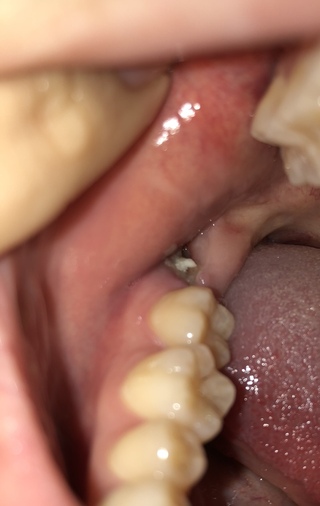

画像注意 親知らず抜歯後の穴の血餅 について これは取っていいですか Yahoo 知恵袋

写真あり 右下親知らず抜歯後の血餅が凹んでいる 歯チャンネル歯科相談室

親知らずの抜歯をしてから6日目です 汚い画像失礼致します 血餅の Yahoo 知恵袋

親知らず抜歯後の歯茎 写真汚いので申し訳ないですが 今日は診療していないので Yahoo 知恵袋